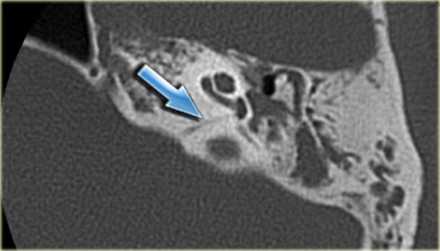

Опухоли эндолимфатического мешка доброкачественные, медленнорастущие, двухсторонние связаны с болезнью Гиппель-Линдау, относящейся группе факоматозов. При КТ видна костная эрозия верхушки пирамиды, а при МРТ головного мозга с контрастировавшем образование хорошо усиливается.

Холестеатомы (эпидермоидные кисты) часто встречаются в области верхушки пирамиды. Их отображение на МРТ зависит от примеси холестерола.

Вестибулокохлеарный нерв (VIII) состоит из 4 пучков. Опухоли происходят обычно из вестибулярной его части. Шваннома - инкапсулированная доброкачественная (градация 1) опухоль, происходящая из дифференцированных неопластических шванновских клеток оболочек периферических нервов. Невриномы ММУ составляют около 3% опухолей головного мозга. Часть шванном (двухсторонние слуховых нервов) связана с НФ 2 типа. Пик частоты между 40 и 60 годами. Растут медленно и крайне редко малигнизируются. Клинические проявления связаны с нарушением функции нерва и компрессией ствола. Шваннома может происходить из любого отрезка по ходу нерва и хорошо прослеживается при МРТ области ММУ. Невринома видна как на Т2-взвешенных, так и на Т1-взвешенных МРТ в виде округлого образования. Невриномы хорошо и равномерно усиливаются после МРТ с введением контрастного вещества. Невриномы области цистерны могут иметь компонент во внутреннем слуховом проходе, особенно, хорошо видимый при МРТ головного мозга с контрастированием. Изредка встречаются невриномы полностью расположенные внутри канальца. Они составляют наибольшую диагностическую сложность при МРТ, требуют тонких срезов и контрастирования. Менингиомы ММУ обычно типично расположены и при МРТ имеют характерную форму и типичные черты при МРТ с контрастированием. Однако редко встречаются внутриканальцевые менингиомы. При МРТ они неотличимы от неврином. Холестеатомы при МРТ имеют смешанную интенсивность сигнала, в зависимости от их содержимого. На диффузионно-взвешенных МРТ холестеатомы обычно яркие.

МРТ головного мозга наиболее информативна в плане выявления опухолей мостомозжечкового угла и кист этой области. Некоторое патологии, такие как расширение водопровода и лабиринтит также хорошо видны при МРТ. КТ лучше демонстрирует состояние внутреннего уха.